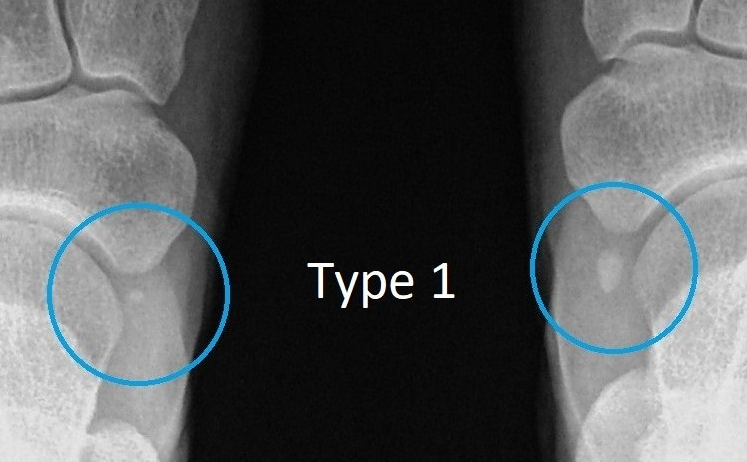

Accessory navicular surgery procedure is a groundbreaking solution for individuals suffering from accessory navicular syndrome, a condition that can cause severe foot pain and discomfort. This innovative surgical option not only alleviates pain but also restores mobility, enabling patients to return to their active lifestyles with confidence.

With advancements in medical techniques and technology, the accessory navicular surgery procedure has become a sought-after treatment. This procedure not only removes the accessory bone but also addresses the underlying issues that contribute to foot pain, ensuring long-lasting relief and improved quality of life.

What is accessory navicular surgery procedure?

The accessory navicular surgery procedure involves the removal of an extra bone in the foot to relieve pain and improve function.

Who is a candidate for this surgery?

Individuals with persistent pain due to accessory navicular syndrome that does not respond to conservative treatments may be candidates.